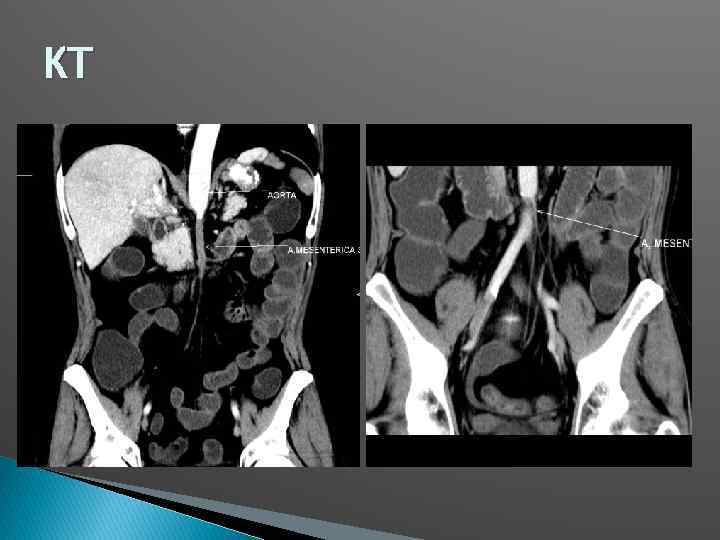

КТ

КТ